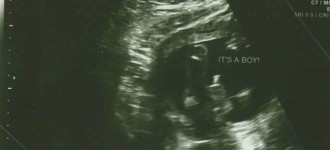

Cuando quedé embarazada de Kung Fu Baby Boy yo ya tenía los nombres escogidos, uno de niña y otro de niño. Si hubiese sido niña se hubiese llamado Eva Luna, el nombre de niño era Bruno.

Nadie pudo opinar y si en algún momento lo hicieron, la verdad